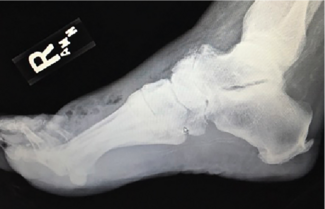

Experienced runners can often feel different effects from heel-to-toe drops of different amounts in shoes, but can this have an effect on heel pain? This author looks at the research of low drop versus high drop, and their potential...